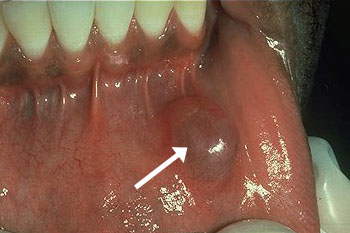

Mucokèle

Een mucokèle of een slijmcyste is een ophoping van speeksel door waarschijnlijk een beschadiging van de afvoergang van de desbetreffende speekselkliertjes. De afwijking komt meestal in de onderlip en mondbodem voor en in zeldzame gevallen kan het ook de wang, bovenlip en gehemelte zijn. De behandeling bestaat uit het weghalen van de zwelling en de omgevende speekselkiertjes.